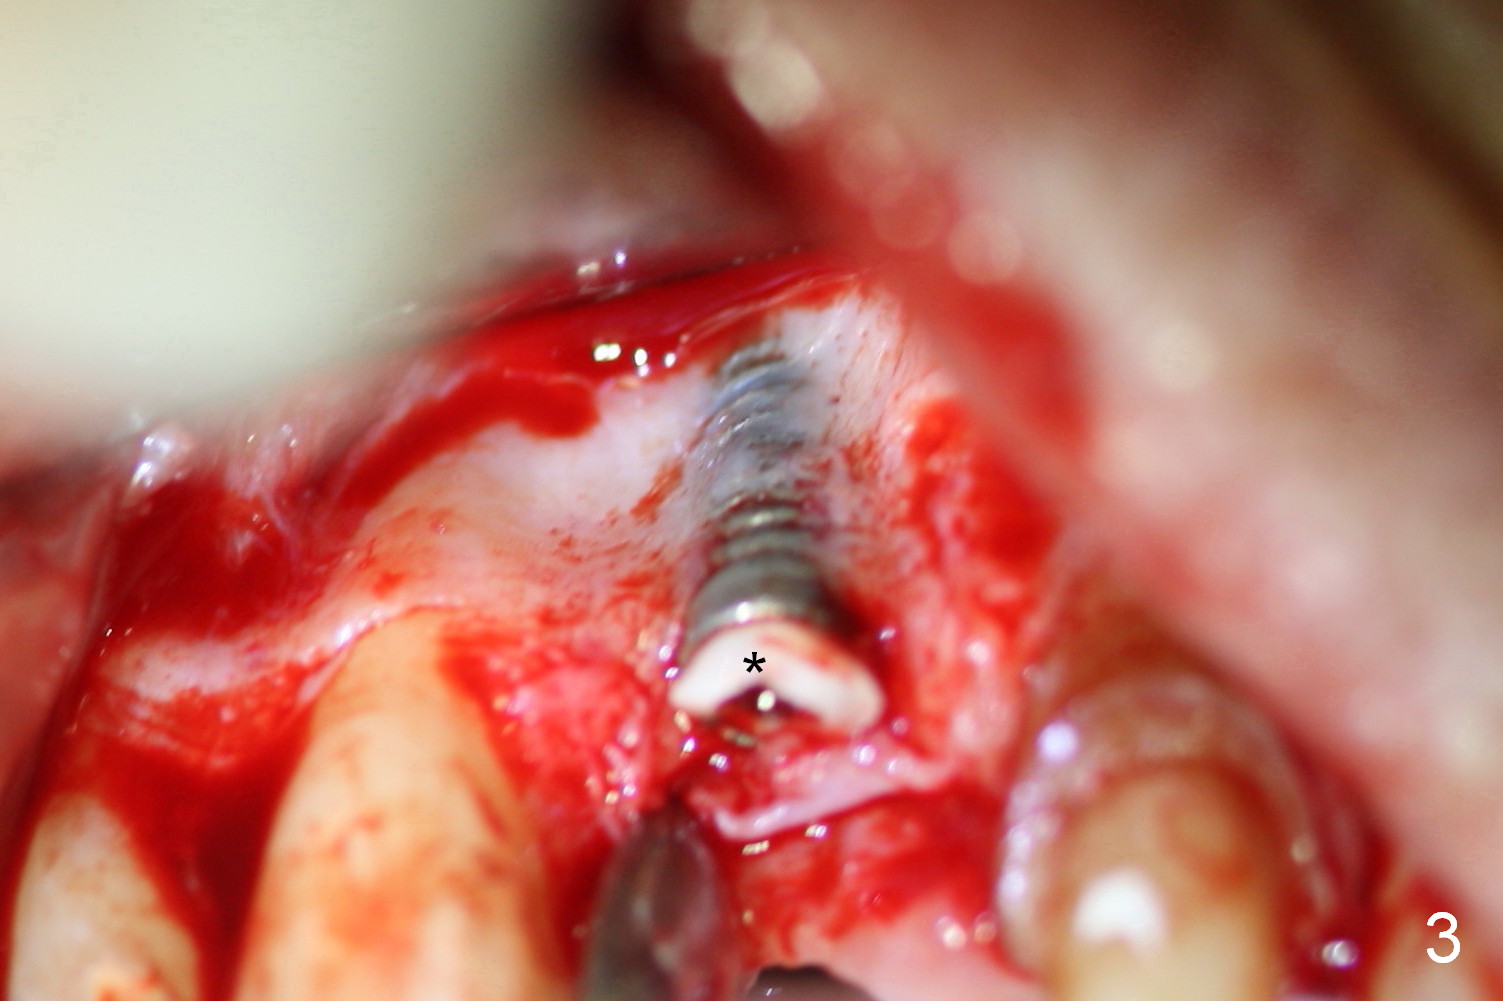

The patient returns for Zirconium abutment retrieval 1 month post its fracture.  When the provisional is removed, the gingival pontic morphology remains (Fig.2).  There is no problem to remove the abutment screw (Fig.1 with its driver), whereas it is difficult to remove the remaining abutment (Fig.2 *) due to limited access.  When the access improves by incision (Fig.3), buccal implant thread exposure is confirmed and the fractured abutment (*) is to be removed easily.  A 15° angled abutment (A) corrects the angulation, but not the position (Fig.4,5, compare to Fig.1 with a driver in place).  After being trimmed, the labial contour of the abutment is equivalent to that of #9 (Fig.6,7), but the margin is higher.  Using an abutment with taller gingival height (from 2 mm to 3 mm) may alleviate the margin issue.